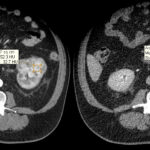

Fase corticomedular y arterial

Esta primera fase ocurre en los primeros 25 a 70 segundos posteriores a la inyección del medio de contraste; la corteza renal, al retener el medio de contraste en este tiempo en los capilares corticales aumenta de una manera intensa diferenciándose de la médula renal, que se encuentra hipodensa.

La fase arterial o corticomedular es esencial para la estadificación, extensión y planificación quirúrgica, si fuese el caso de la neoplasia encontrada, ya que ofrece un mejor detalle vascular (opacificación de los vasos), una mayor definición anatómica y de lesiones vascularizadas en el hígado, el bazo o el páncreas, consideradas dentro del contexto de una metástasis (Fig. 2).

Los errores diagnósticos que pueden presentarse durante esta fase se asocian a lesiones de pequeño tamaño; en el caso de un tumor hipervascularizado pequeño aumentaría su atenuación en la misma medida en que lo haría la corteza. Otro error que puede ocurrir es con los tumores pequeños que se localizan hacia la médula, ya que por su ubicación se mantendrían hipodensos durante esta fase 3-4.